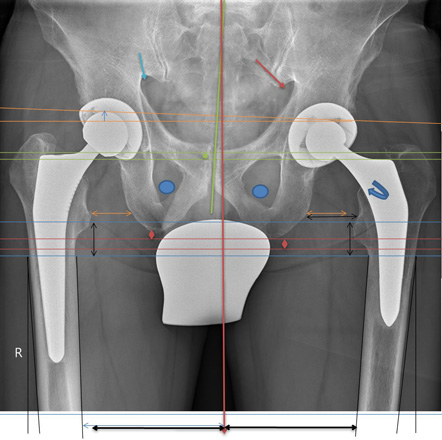

Becken Bild 1

Anhand der Original Aufnahmen werden Spannungsbedingte Ausweichhaltungen auf den folgenden Seiten sichtbar gemacht.

6848180

1.1

Aufnahme zeigt eine Verdrehung der linken Seite, anhand der Beckenlöcher.

Zudem muss das Becken seitlich verschoben sein.

Sichtbar anhand der Beinstellungen und der Verdrehung des Schenkelhalses.

Weiter wird ersichtlich, dass links das Becken hochgedrückt wird.

Eindeutig am Beckenspalt zu erkennen, das der Oberkörper nach links ausweicht und somit das Becken in der Höhe verzieht.

Auch drückt es oberhalb der Hüftkugel rechts das Becken über den Zug der seitlichen Oberkörper Haltung hoch und verzieht das Becken.

1.2

Wurde ein neues Hüftgelenk eingebaut, wegen den Schmerzen in der Leiste.

1.3

Nun sieht man, dass die Bein- und Gelenk-Stellung nicht übereinstimmt.

Die Schmerzen sind geblieben.

Abbildung Hüft / Teil Rücken / Teil Beine von hinten aufgenommen

1.5

1.6

Hüft mit Strichen Pfeilen Kreise sichtbar gemacht

Oberkörper weicht trotz Hüftgelenk Ersatz blau eingesetzte Striche aus.

Anhand der Gesässfalten wird auch der Beckentiefstand ersichtlich.

Über die Grüne Linie sieht man wie die rechte Seite geknickt wird.

Auf der linken Seite wird die Überdehnungsspannung sichtbar.

Würde die Ganz-Körper-Statik Vermessung eingesetzt, würde die Diagnose schnell und präzise die Ausweichhaltungen aufzeigen.

Würde die Ganz-Körper-Statik Vermessung bei den bildgebenden Verfahren eingesetzt, könnten Fehldiagnosen verhindert werden. Dies würde die Ursache der Skelett Ausweichhaltungen als Ursache der Muskelfehlspannungen aufzeigen.

1.7

Trotz dem wurde das andere Hüftgelenk auch noch ausgewechselt.

Trotz Operationen sind die Schmerzen geblieben.

Beachtet man das Becken und die Gelenk-Stellungen sieht man nun auf der rechten Seite eine Verdrehung des Beckenlochs.

Der Beckenspalt ist immer noch hochgezogen. Durch die Verdrehung quetscht nun die linke Seite.

Man hat die Belastung verschoben.

Bei der Statik Kontrolle wurde der Beckentiefstand und der damit verbundenen seitlichen Oberkörper- Ausweichhaltung nicht beachtet.

1.8

DICOM-30

Würde die Ganz-Körper-Statik Vermessung bei den bildgebenden Verfahren eingesetzt, könnten Fehldiagnosen verhindert und zudem viele Kosten gespart werden. Dies würde die Ursache der Skelett Ausweichhaltungen als Ursache der Muskelfehlspannungen aufzeigen.